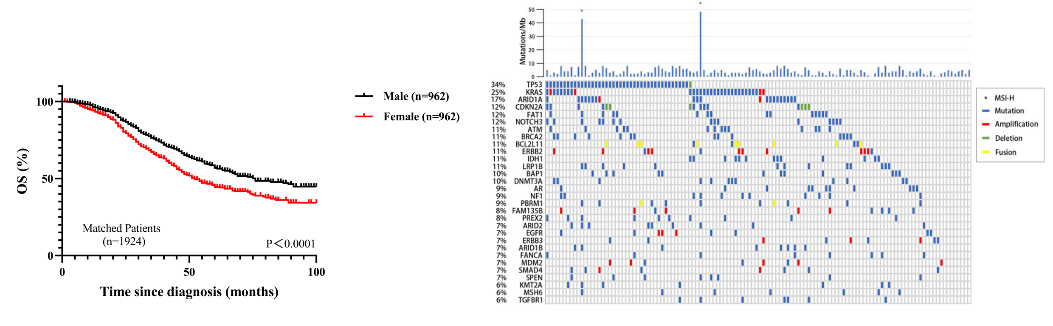

张宇华表示,门诊中首诊的肝癌患者只有20-30%有手术机会,剩余百分之七八十的首诊患者因为发现时已经是中晚期,很多已经没有了手术机会,而手术切除是肝癌患者目前唯一可能获得长期生存的治疗选择。

“还有一部分肝癌患者是由脂肪肝发展而来的。” 张华宇说,长久以来,人们都以为肝癌很难治愈,尤其是中晚期,一旦被确诊,感觉是被判了死刑,“实际上,现在对于肝癌的治疗发展很快,有很多手段,除了手术之后,对那些初诊不能手术的患者,还可以采用转化治疗,包括介入治疗,靶向免疫治疗等等,也就是先“保守”治疗,将肿瘤缩小,再寻求手术切除的机会。”